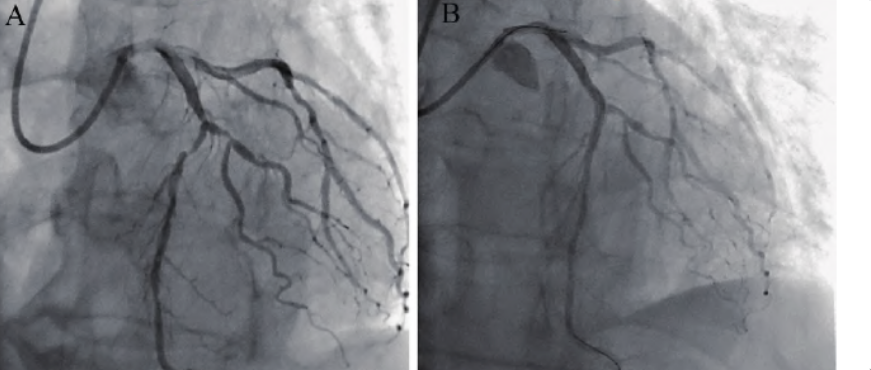

▲ 冠脉造影或尸检证实冠脉栓塞。

10、梗死部位特殊:左回旋支闭塞50%病例常规12导联心电图无改变,单纯后壁心梗、右室心梗常规12导联心电图可无明显改变。